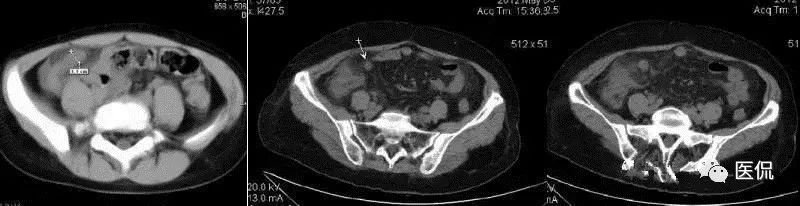

(2)CT:阑尾扩张,管径>6mm,壁增厚,增强强化。阑尾周围炎,周围(脂肪)“条纹征”即周脂肪内斑点/条纹状模糊英、局部筋膜增厚、系膜密度增高等。阑尾粪石,其他有盲肠增厚、阑尾周液体积聚、“箭头征”(肠道内造影剂汇集在盲肠尖端(阑尾起始部)形成箭头样或鸟嘴样改变)。

(2)CT:右下腹/盆腔囊性肿块,壁薄或厚,增强环形强化,内部可见粪石;也可为边界不清、密度不均软组织影,强化不明显。肿块与盲肠关系密切,与周围结构粘连,内可见小气泡/气液平面。临近肠曲反射性淤积,可伴气液平面。